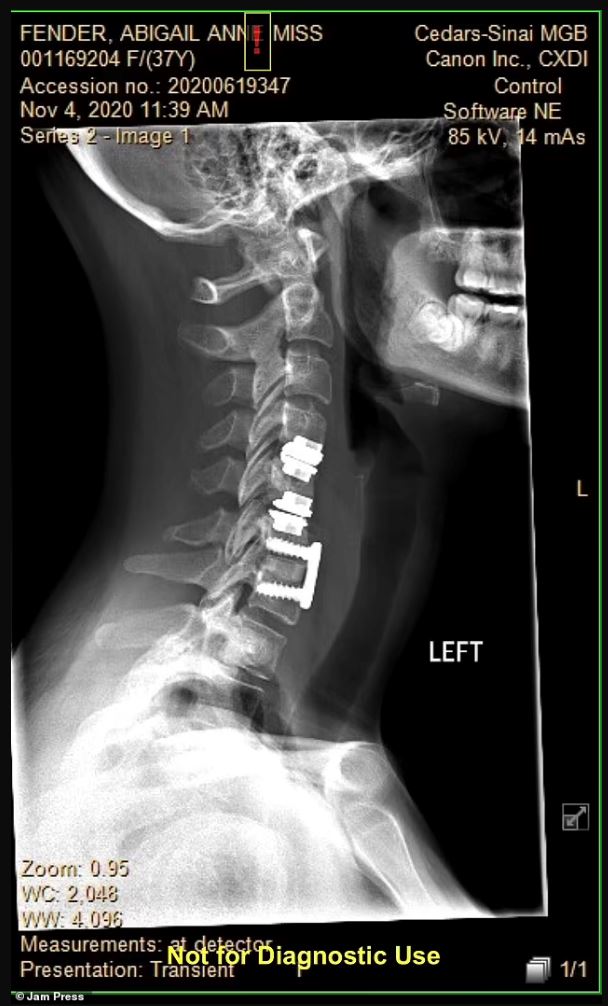

Abby Fender berdepan situasi aneh ini seminggu selepas dia menjalani pembedahan bagi membetulkan herniated disc.

Disahkan menghidap sindrom loghat asing (FAS), Abby, 39, berdepan keadaan yang hanya berlaku satu dalam 100 kes di seluruh dunia.